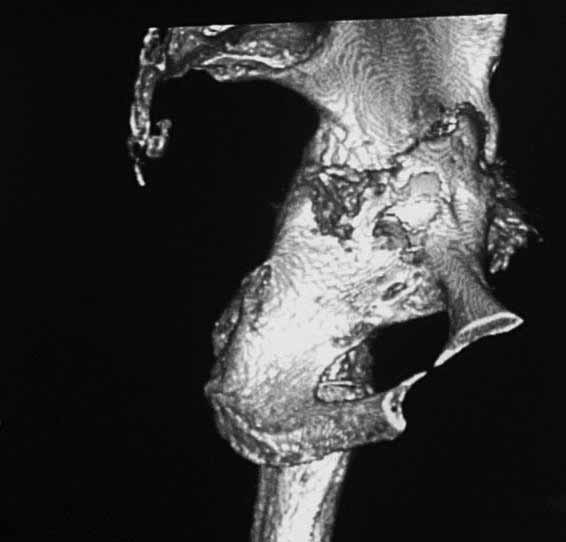

Уважаемые коллеги. Хотелось бы услышать мнения и советы по представляемому случаю. Пациентка 45 лет. Бесцементное эндопротезирование левого тазобедренного сустава 6 лет назад (впадина RM, Mathys, металл-металл, ножка Зульцеровская). За 10 лет до протезирования – коррегирующая остеотомия бедренной кости, которая не срослась в течение года до удаления пластины, а затем срослась в течение 3 месяцев иммобилизации в кокситной повязке. После протезирования получилось наблюдать пациентку почти постоянно, поскольку через 2 года синтезировал ей лодыжки на оперированной стороне, затем, через несколько месяцев удалил фиксаторы, а в 2009г. резецировал мениск на противоположной стороне. Боли все эти годы не беспокоили. Пациентка чуть выше среднего роста, вес тела нормальный. Физические нагрузки переносила хорошо. Работает на 7 этаже без лифта. Год назад экстирпация матки по поводу лейомиомы больших размеров. Несколько месяцев назад появились боли в области левого тазобедренного сустава. При рентгеновском и КТ исследованиях (июль с.г.) – нестабильность тазового компонента. От предложенной замены протеза пациентка на тот момент, слава богу, отказалась. Через какое то время боли в области левого тазобедренного сустава практически полностью прошли, а около 2 месяцев назад появилось ощущение патологической подвижности таза и боли в паху справа, которые через некоторое время уменьшились, а потом снова усилились после значительных физических нагрузок (много ходила по песку на пляже, носила тяжести). Ежедневно принимала диклофенак. На рентгенограммах – переломы правой лонной кости. Сейчас госпитализирована из-за болей в паху справа. Боли слева не беспокоят. На фоне снижения нагрузок в стационаре боли значимо уменьшились. Способна ходить без средств дополнительной опоры.В анализах крови чуть повышены трансаминазы и гамма-ГТ, моча без особенностей.

Вопросы: -правильно ли я расцениваю переломы как стрессовые на фоне неполноценного таза (pelvic insufficiency stress fractures)? -Можно ли так же расценить ситуацию на стороне протеза и, соответственно, не торопиться с ревизией, рассчитывая на вторичную стабилизацию? Уж больно не хочется менять ножку. -Если думать о ревизии, то когда? На представленных снимках тазобедренный сустав до и сразу после операции, затем 2 снимка 2009г., когда ничего не беспокоило, затем КТ 2-х месячной давности и вчерашние рентгенограммы обоих тазобедренных суставов.

Сергей, очень возможно, что перелом и стрессовый, но мне видится, что его причина в нестабильности чашки. Дело в том, что в отличии от ножек, чашка при своей дестабилизации болит гораздо меньше и больные терпят до последнего.

При сравнении рентгенограмм можно увидеть насколько чашка переместилась от места своего первичного расположения. От опрокидывания ее удерживают конструкционные элементы "рожки". Без них ситуация, возможно, уже была бы катастрофической (чашка в тазу). Думаю надежды на вторичную интеграцию, могут быть обмануты и ревизии не избежать.